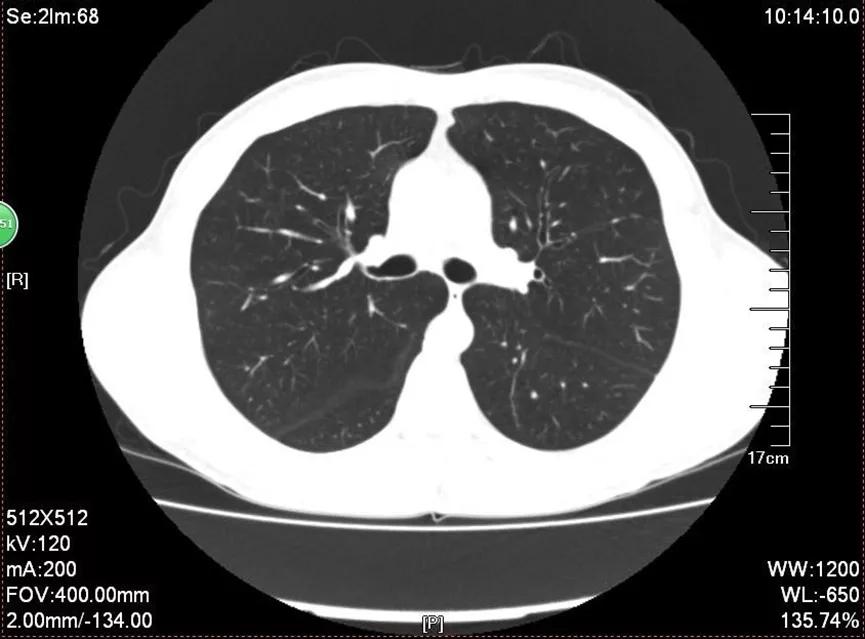

其他检查结果情况为:血常规中Hb:121g/L、PLT:165×109/L。肝功能及生化基本正常;凝血四项正常;降钙素原:<0.05ng/ml;B型钠尿肽前体:4776pg/mL;抗中性粒细胞胞浆抗体为阴性。腹部B超: 腹腔积液 ,脾稍大,脾门部低回声团,未排副脾可能,余未见异常。胸部CT:肺实质未见异常(图1),心影增大(以左室、右房为主), 心包少许积液 ,右侧心膈角、腔静脉后、两腋窝多个淋巴结,拟反应性增生。

图1:胸部CT肺实质未见异常